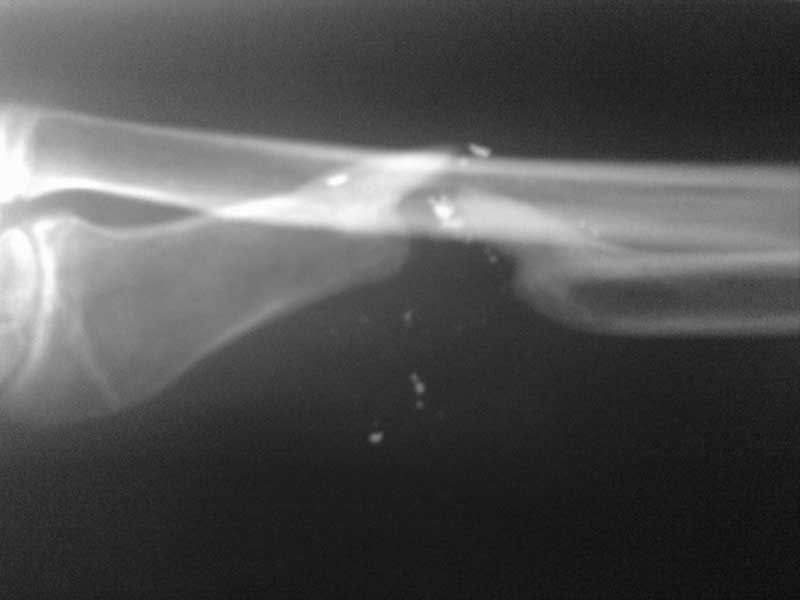

Больной 16 лет, в июле 2011 получил в результате неосторожного обращения с огнестрельным

оружием, дробовое огнестрельное ранение левого предплечья. Первая помощь оказана в

условиях ЦРБ, раны зажили, кожа чистая, рубцы состоятельны. Ангионевротических

расстройств нет. Интересует мнение коллег по тактике лечения в плане замещения костного

дефекта. Cпасибо, заранее.